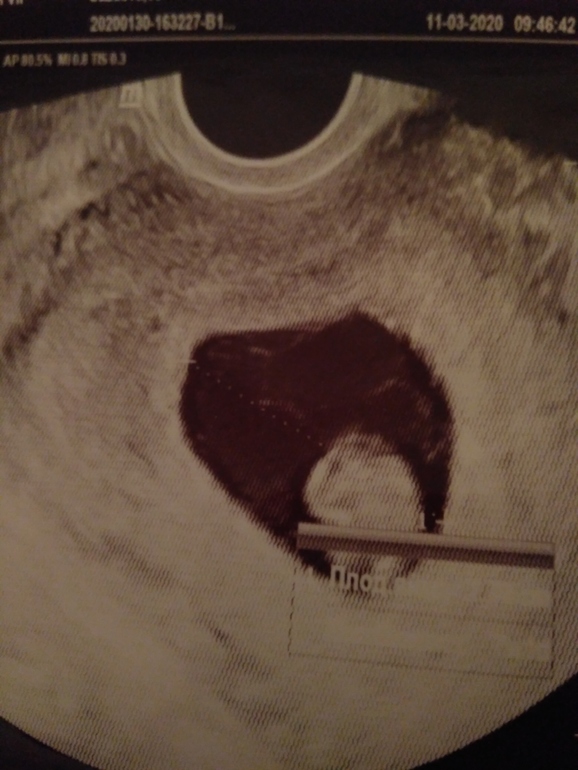

Я БЕРЕМЕННА !Девочки всем привет🌷 Сегодня я наконец таки дождалась наше первое узи - я слышала как бьётся сердечко у моей крохи💓 как же я счастлива🤗 дай Бог, чтобы малыш развивался благополучно 🙏 у нас теперь есть наши первые фото💝 вот одно из них👇